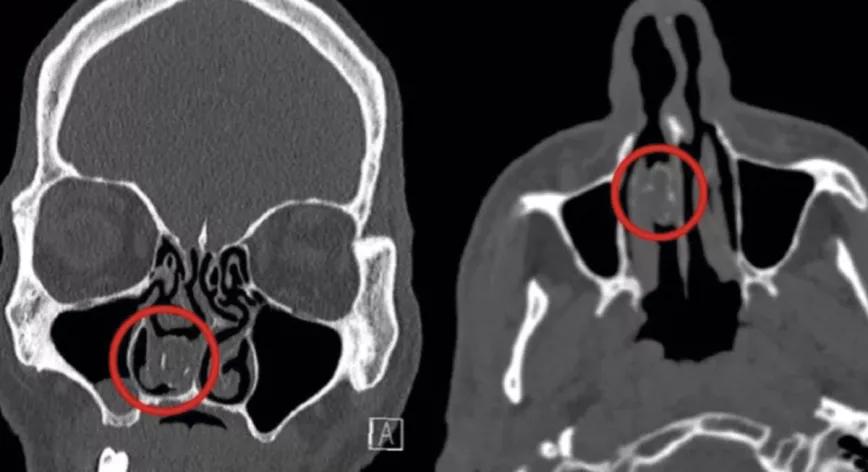

En Australia un equipo de médicos extrajo un pequeño paquete de marihuana de la nariz de un hombre de 48 años. El descubrimiento se produjo durante una prueba médica de escáner con la que los médicos pretendían examinar el cráneo del afectado.

El hombre acudió a un centro médico por dolores de cabeza y tras explicarles que tenía antecedentes de obstrucción nasal e infecciones decidieron practicarle un escáner del cráneo. Los médicos descubrieron que el paciente tenía alojado un objeto extraño de 19 mm por 11 mm en el interior de su fosa nasal derecha y cuando lo extrajeron descubrieron que se trataba de un globo de goma que contenía restos de materia vegetal descompuesta. Entonces el hombre recordó un episodio ocurrido en el pasado, cuando estando ingresado en prisión su pareja de entonces le llevó algo de marihuana en una visita a la cárcel. El hombre introdujo la marihuana en un globo y se la metió por la nariz para eludir los controles de la cárcel. Para que pasara desapercibida el hombre acabó empujando tanto el globo que pensó que había acabado por tragárselo y se olvidó de la marihuana.

El episodio de la cárcel ocurrió hace 18 años, tiempo que el paquete con marihuana había permanecido en el interior de las fosas nasales del sujeto. Semanas después de la extracción el paciente dijo que las molestias habían desaparecido. El caso fue publicado en un informe para la revista médica BMJ Case Reports.